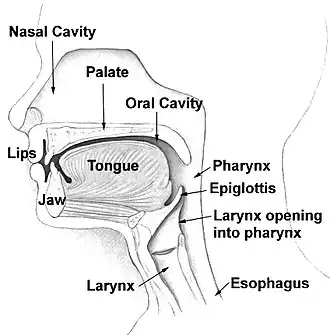

The nasal cavity is a large , air-filled space above and behind the nose in the middle of the face. The nasal septum divides the cavity into two cavities,[1] also known as fossae.[2] Each cavity is the continuation of one of the two nostrils. The nasal cavity is the uppermost part of the respiratory system and provides the nasal passage for inhaled air from the nostrils to the nasopharynx and rest of the respiratory tract.

The floor of the nasal cavities, which also form the roof of the mouth, is made up by the bones of the hard palate: the horizontal plate of the palatine bone posteriorly and the palatine process of the maxilla anteriorly. The most anterior part of the nasal cavity is the nasal vestibule.[4] The vestibule is enclosed by the nasal cartilages and lined by the same epithelium of the skin (stratified squamous, keratinized). Within the vestibule, this changes into the typical respiratory epithelium that lines the rest of the nasal cavity and respiratory tract. Inside the nostrils of the vestibule are the nasal hair, which filter dust and other matter that are breathed in. The back of the cavity blends, via the choanae, into the nasopharynx.

The two nasal cavities condition the air to be received by the other areas of the respiratory tract. Owing to the large surface area provided by the nasal conchae (also known as turbinates), the air passing through the nasal cavity is warmed or cooled to within 1 degree of body temperature. In addition, the air is humidified, and dust and other particulate matter is removed by nasal hair in the nostrils. The entire mucosa of the nasal cavity is covered by a blanket of mucus, which lies superficial to the microscopic cilia and also filters inspired air. The cilia of the respiratory epithelium move the secreted mucus and particulate matter posteriorly towards the pharynx where it passes into the esophagus and is digested in the stomach. The nasal cavity also houses the sense of smell and contributes greatly to taste sensation through its posterior communication with the mouth via the choanae.